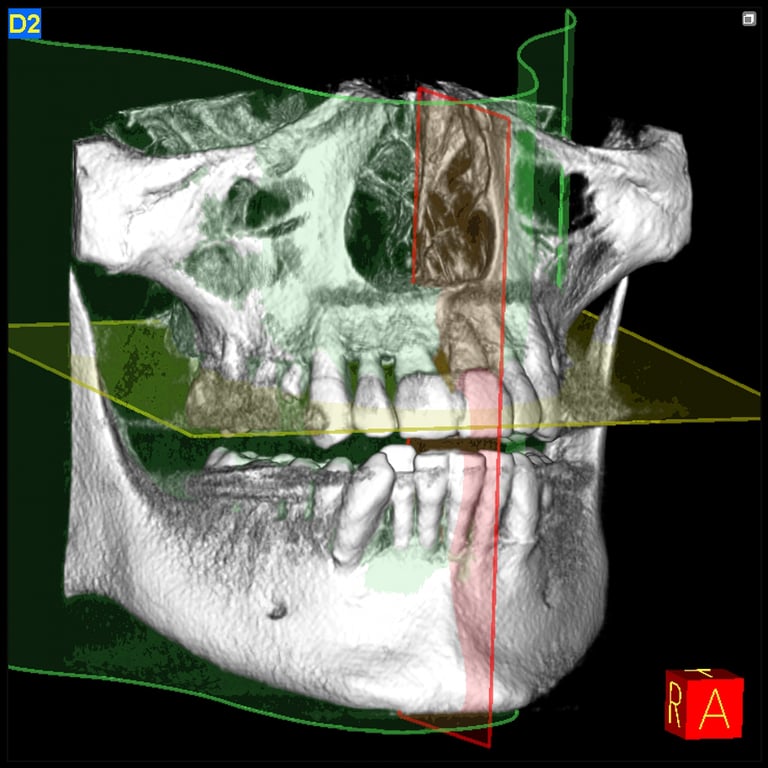

Lisa from USA: Missing all teeth

After: All on 4 upper and lower jaws at Amaris Dental Clinic